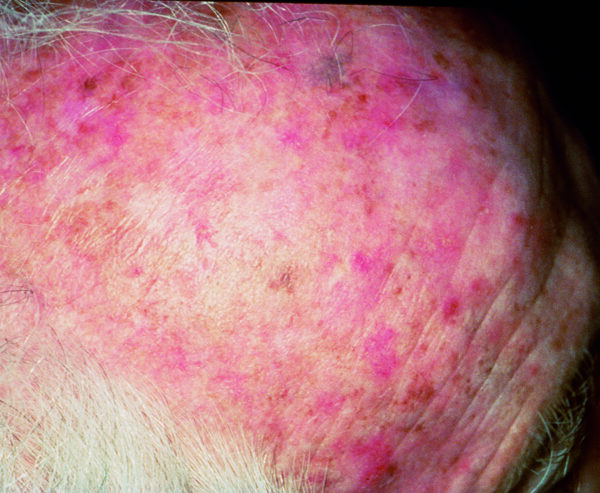

Actinic Keratosis (AK) Photos

Actinic keratosis on head or neck. Photo: International Skin Imaging Collaboration at isic-archive.com